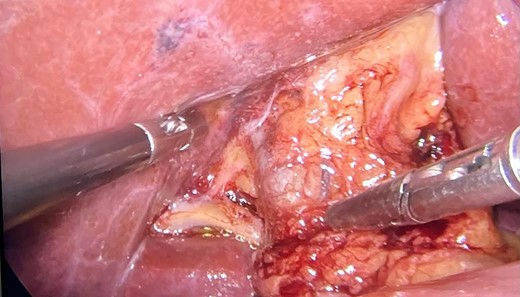

The patient underwent videolaparoscopy in order to perform cholecystectomy, however, no gallbladder was identified in its anatomical site. The common bile duct and hepatic artery were easily dissected and neither the cystic duct nor the cystic artery were identified (Figs 2 and 3). The patient was discharged on the same day of surgery.

Image showing the gallbladder anatomical site and hepatic hilum without normal nor shrunken gallbladder; CBD, common bile duct; RHD, right hepatic duct; LHD, left hepatic duct.